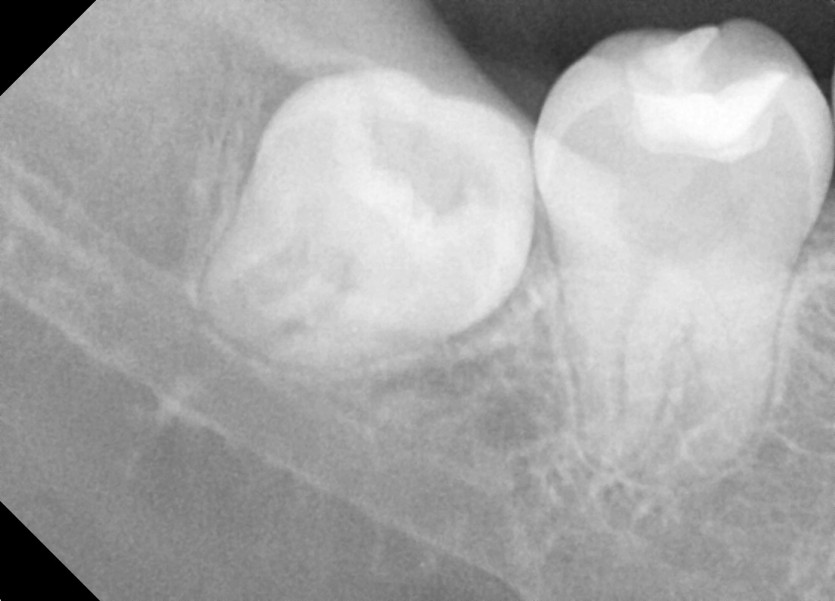

#38,48 사랑니 발치

구강 외과 전문의가 당일 발치했습니다.